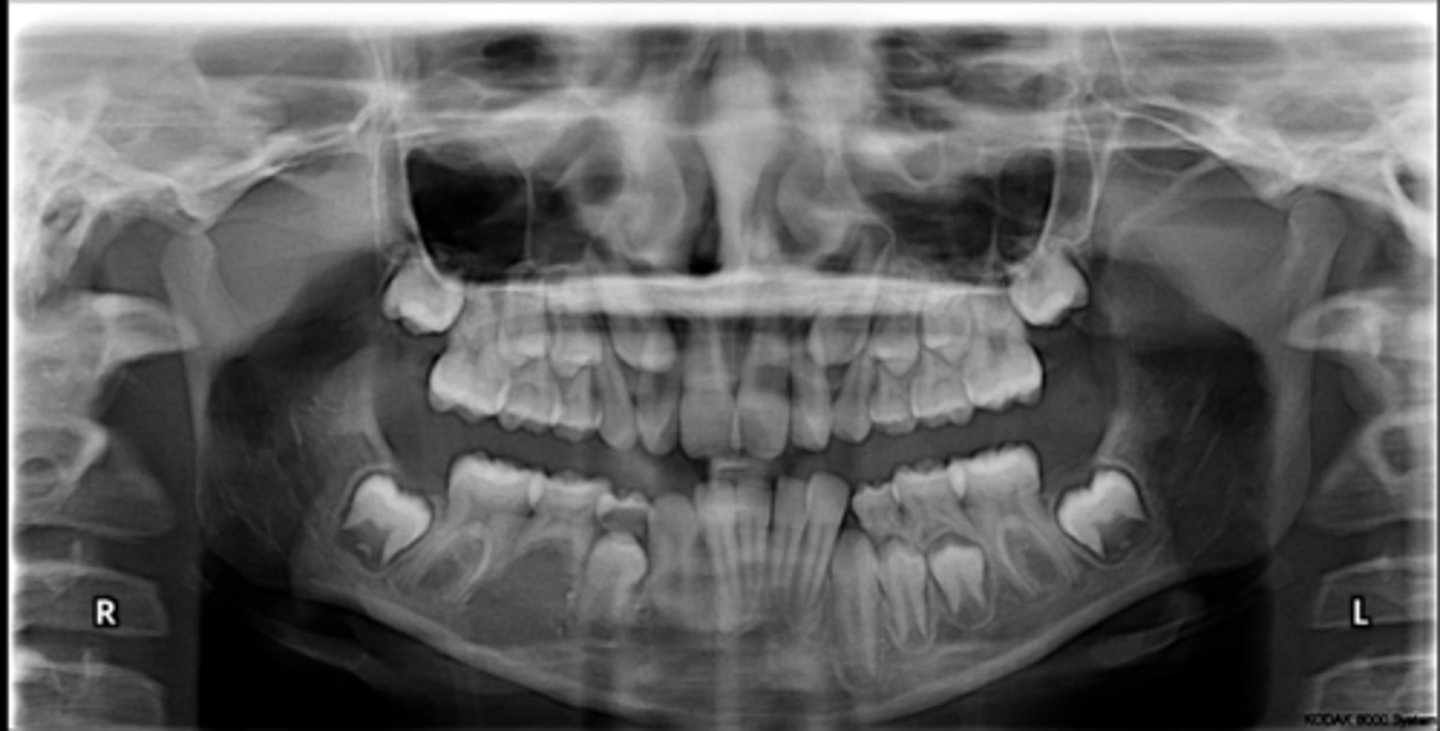

Right primary canine

Are there retained primary teeth?

Yes

Are there any impacted teeth?

Are the condyles symmetrical?

Is there a dilacerated root?

No

The mandibular left side has normal premolar/canine eruption, but the rigth side is abnormal.

Is the eruption pattern of this patient normal or not?

Are there any supernumerary teeth?

Are there any retained primary teeth?

Not at this stage

Are there impacted teeth?

Yes, within the range of normal

Symmetric condyles?

Yes - maxillary first molar

Dilacerated roots?

Yes - laterals

Are there congentially missing teeth in the maxillary arch?

Yes - an incisor

Are there congenitally missing teeth in the mandibular arch?

Yes - upper right near the premolar

Any impacted teeth?

Can't see, so can't say